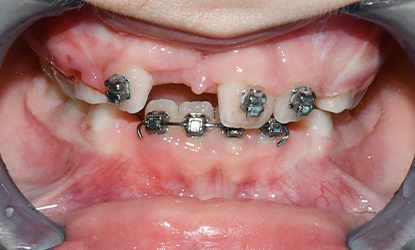

>   Autotransplantacja w miejsce 11 – przeniesienie własnego zęba pacjenta w celu uzupełnienia brakującego zęba w przednim odcinku szczęki.

W przypadku naszej pacjentki celem leczenia było szybkie przywrócenie funkcji narządu żucia oraz trwała odbudowa brakującego zęba w przednim odcinku szczęki. Po analizie dostępnych opcji zdecydowano się na autotransplantację dolnego zęba przedtrzonowego, który znajdował się w odpowiedniej fazie rozwoju korzenia.

Utracony ząb to górny lewy siekacz przyśrodkowy (21), który został zastąpiony przez dolny ząb przedtrzonowy. Przeszczep z fragmentem kości został precyzyjnie umieszczony w przygotowanej loży kostnej.

Po stronie dawcy, czyli w miejscu usuniętego zęba przedtrzonowego, założono specjalny aparat ortodontyczny, który stabilizował przestrzeń i zapobiegał przesunięciom sąsiednich zębów.